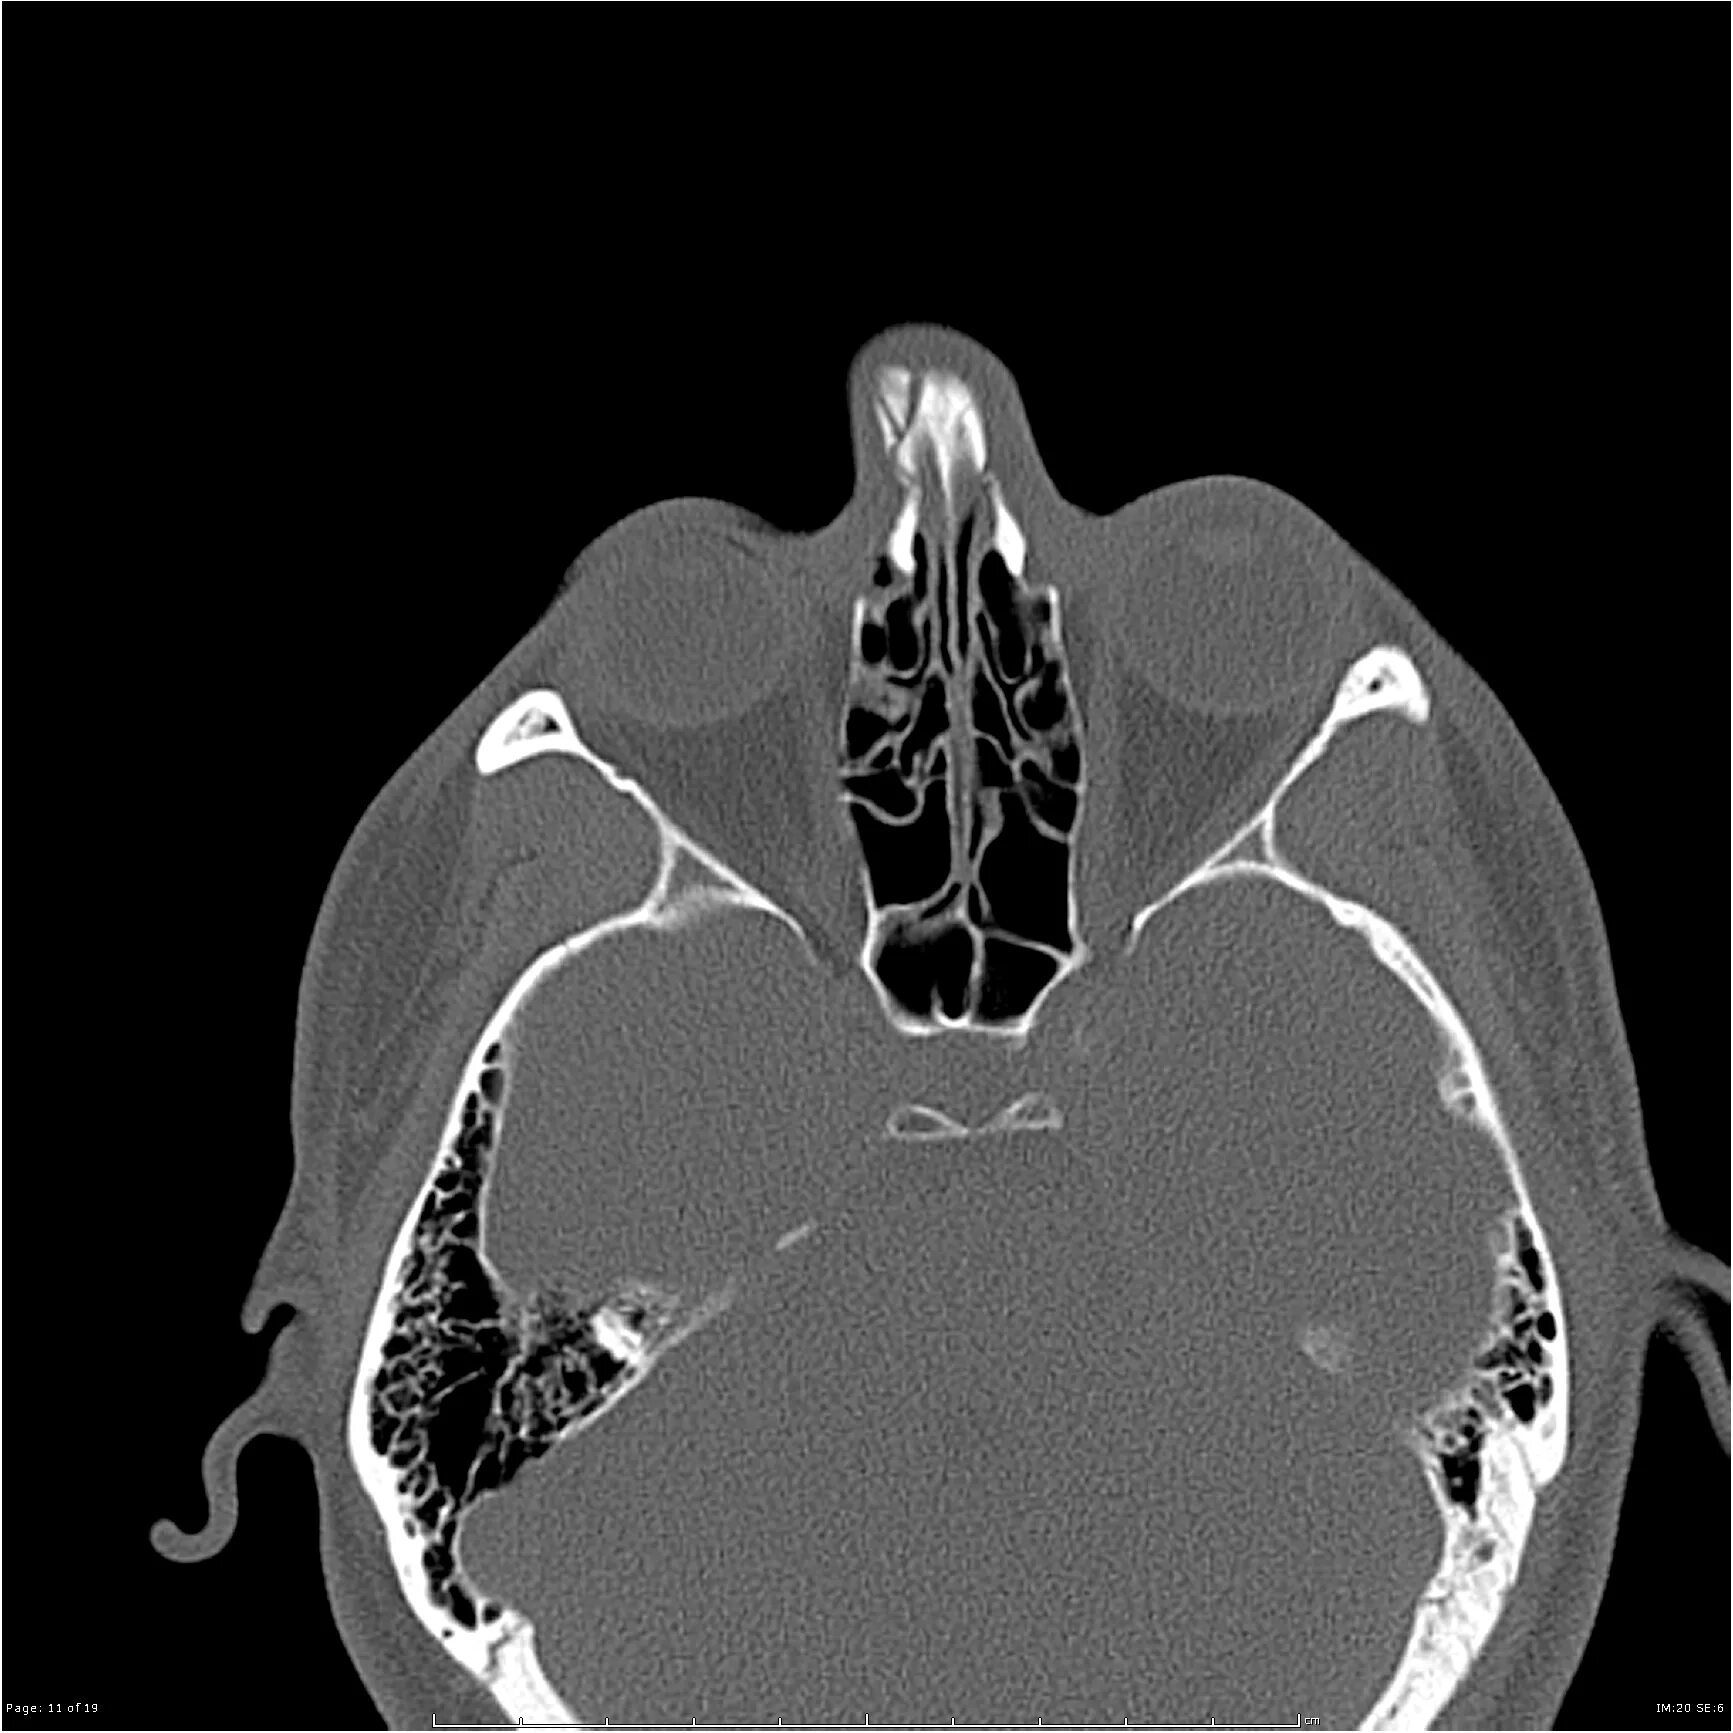

Кт онп что это